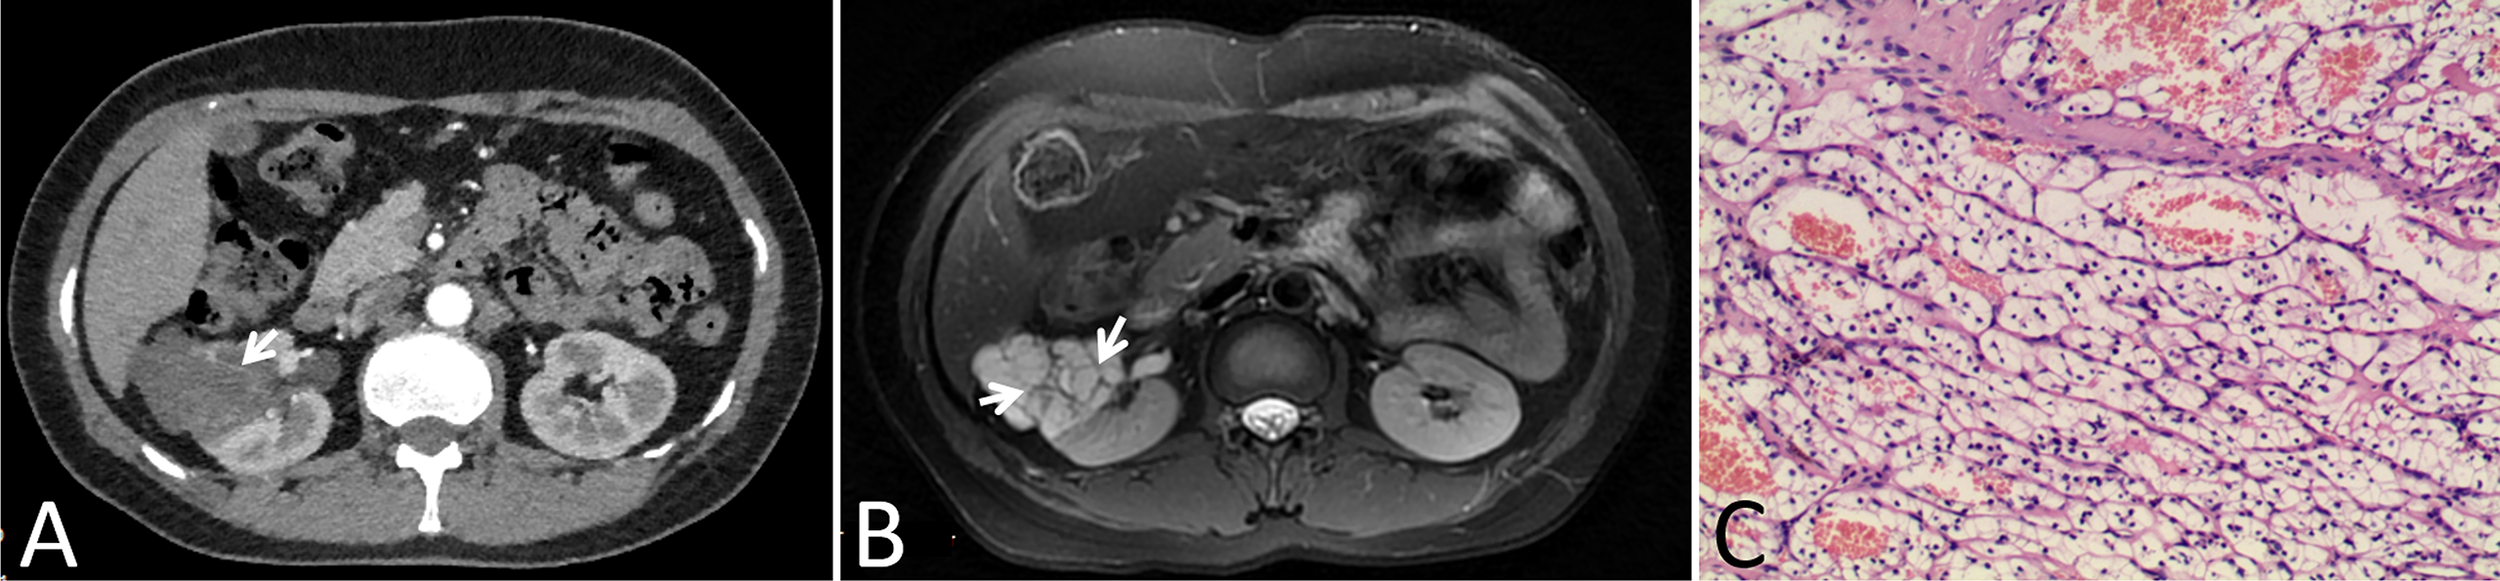

In our cohort, 87 lesions had both CT and routine MRI images, and MRI demonstrated more septa than did CT in 12 of 87 (13.8%) lesions (Figure 2). In one lesion, the cystic mass was classified as measurable enhancement of the wall on the enhanced CT because of the wall obscured by the high density calcification. Since calcification would not be depicted on the MRI, this suspected case of “pseudoenhancement” on CT has no measurable enhancement of the wall on enhanced MRI (Figure 3). Solid components of 13 cystic masses showed high signal intensity on DWI, all of which were malignant lesions (Figure 4).

Figure 2

Images in a 46-year-old woman with a cystic mass in the right kidney. (A) Axial contrast-enhanced CT image shown a complex cystic mass that contained a few thin septa (arrow), (B) Axial T2-weighted MR image shown more septa (arrows) within the lesion than were depicted on the CT image, (C) This lesion was surgically removed and determined to be a renal clear cell carcinoma with cystic changes and glassy changes.